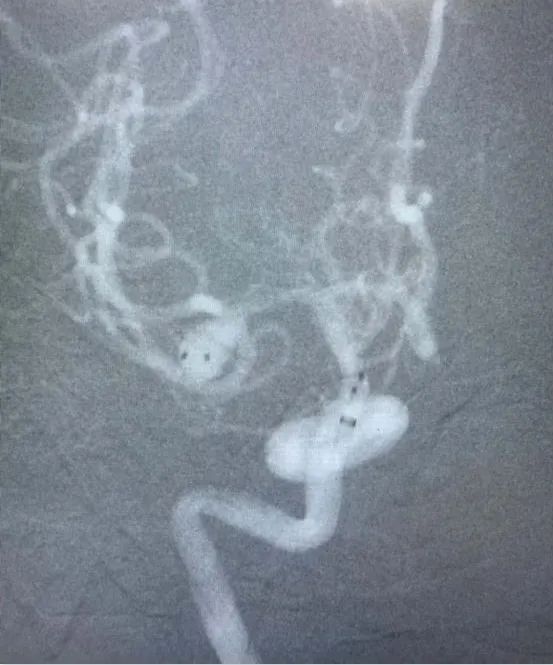

近日,省人民医院神经外科为一位高龄动脉瘤患者施行了介入治疗,成功栓塞了破裂的大脑中动脉瘤。患者因突发晕厥后头痛不适入院,急诊行颅脑CT检查提示蛛网膜下腔出血,行颅脑CTA检查后证实患者存在右侧大脑中动脉瘤。患者高龄,既往基础病多,高血压病、糖尿病、冠心病、双侧颈动脉硬化、双侧腹股沟疝术后等,手术风险较大,经家属签字同意后,当日急诊全麻下行“右侧大脑中动脉瘤介入栓塞术”,术中见血管迂曲明显,导管到位艰难,经过努力,手术顺利结束。术后予多次腰椎穿刺术释放血性脑脊液,患者头痛头晕症状渐缓解。患者住院治疗10天后顺利康复出院,未留后遗症。

动脉瘤主要有两种治疗方式:开颅手术和介入栓塞。两种方法比较,介入栓塞手术时间短、康复快、不需开颅、可同时治疗多个动脉瘤,适合高龄、分级高的患者,其中血管内弹簧圈栓塞术是颅内动脉瘤最常见的一种介入治疗方式,随着介入新材料、技术的不断进步,介入栓塞的优势日渐明显。